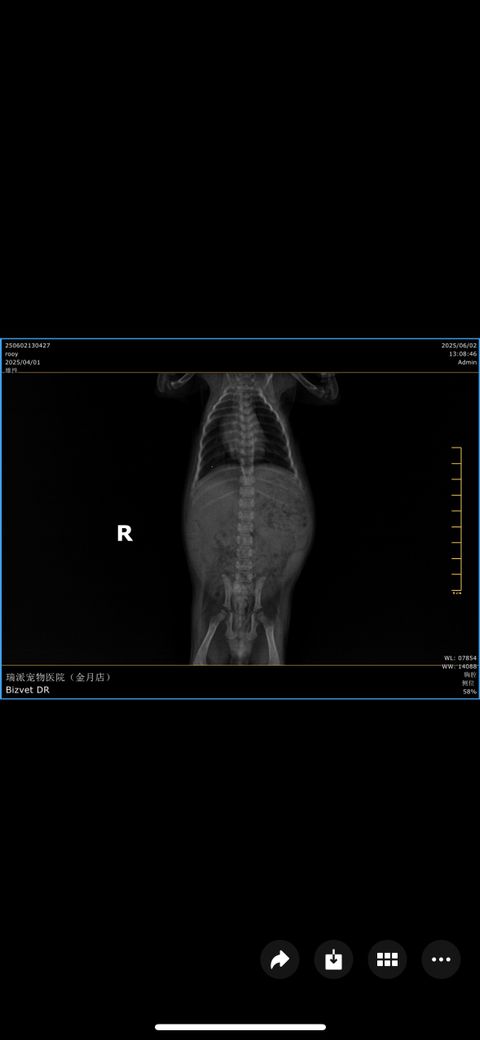

순서대로 2일 간격 엑스레이 사진입니다 ㅠ

점점 안좋아 지는게 맞나요?!

기침은 계속해요.. 의사말로는 마지막 오늘 엑스레이 보고 폐의변화가 있어 숨쉬기 힘들어 할꺼다 하는데 ㅠ 여기가 중국이라서 제대로 치료가 되는지 걱정입니다

폐 전엽부가 다 먹혀버린 매우심한 세균성 폐렴 혹은 인플루엔자 감염이 의심됩니다.

집중적인 처치가 필요한 상태이니 주치의와 잘협의하게 집중 처치하시기 바랍니다.